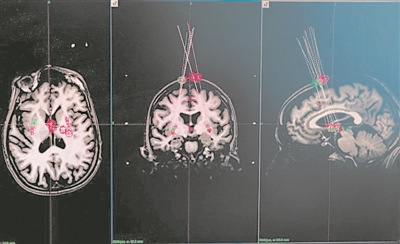

上图展示了瑞典斯科讷大学医院科学家利用一根针头,将细胞移植到人脑中,以治疗帕金森病。下图则显示了科学家根据脑部MRI扫描图像确定针头将细胞送往何处。图片来源:英国《自然》网站

在众多的临床试验中,有12项专注于利用干细胞治疗帕金森病,29项针对眼病,尤其是与年龄相关的黄斑变性。

值得关注的是,今年1月有媒体报道,中国在iPSC衍生细胞疗法治疗帕金森病领域取得了突破性进展。由上海市东方医院刘中民教授团队与合作伙伴联合开展的临床研究显示,受试者在治疗12个月后,运动功能与生活质量均得到显著改善。